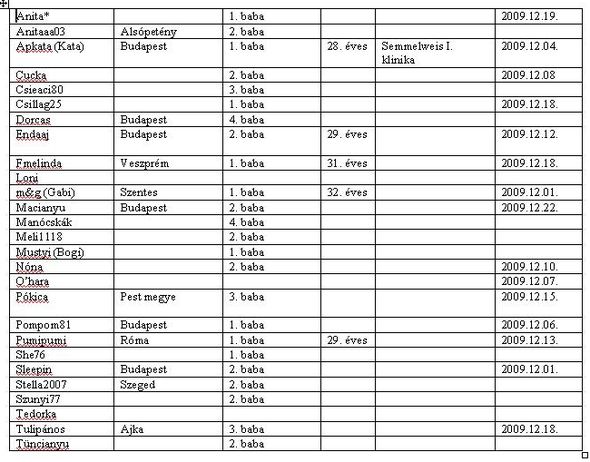

Pókica

Pókica írására böngésztem, itt a cikk, valamint a felsorolás, melyik kórházakban ingyenes. Ebbe estem én bele

A program jelenleg már fut, az ingyenes Down-kór-szűrés az alábbi intézményekben, központokban érhető el: Székesfehérvár - Család- és Nővédelmi Központ, Cegléd - Toldy Ferenc Kórház és Rendelőintézet, Szentes - Városi Kórház, Mohács - Városi Kórház, Marcali - Városi Kórház, Nyíregyháza - Jósa András Megyei Oktató Kórház, Fonyód - Egészségügyi Kht., Mosonmagyaróvár - Városkapu Egészség Centrum. Budapesten a Margit Kórház, a Szent István Kórház, a Szent Imre Kórház, a Bajcsy-Zsilinszky Kórház, az Állami Egészségügyi Központ és a Szent Rókus Kórház kötött együttműködési megállapodást Magzati Diagnosztikai Központtal. További egészségügyi intézményekkel is folyamatban van az együttműködés kialakítása.